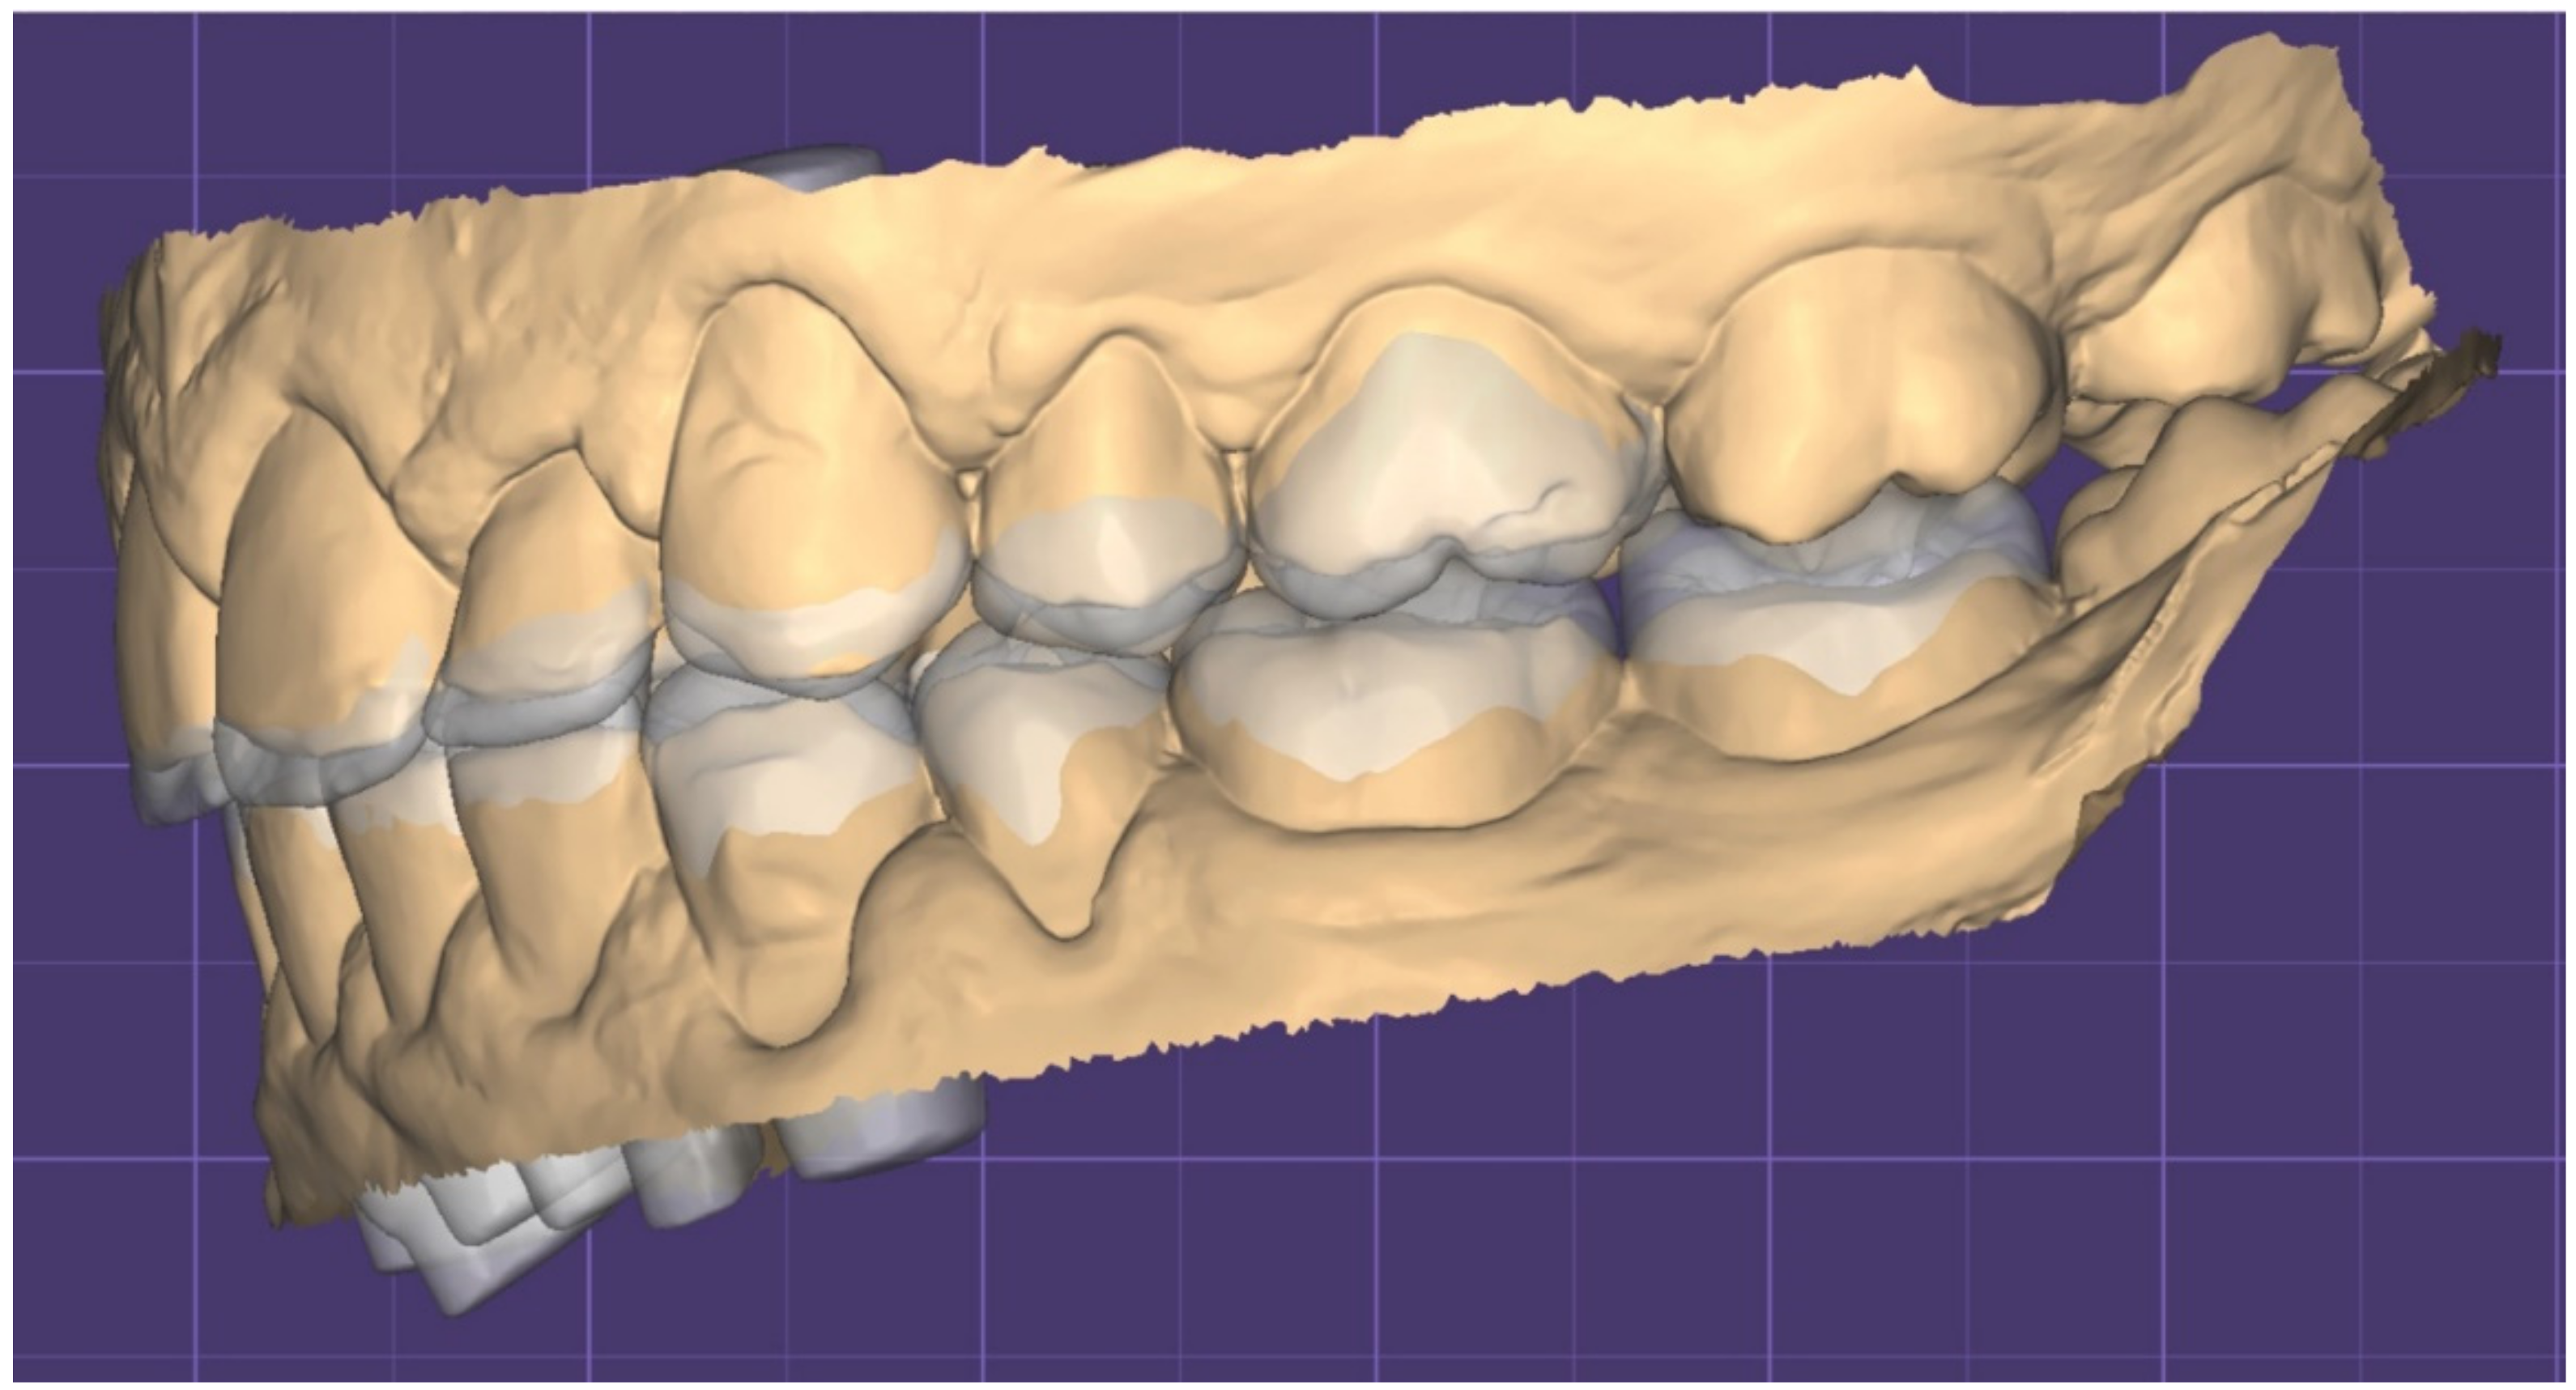

2.1. Planning Phase

2.2. Restorative Phase